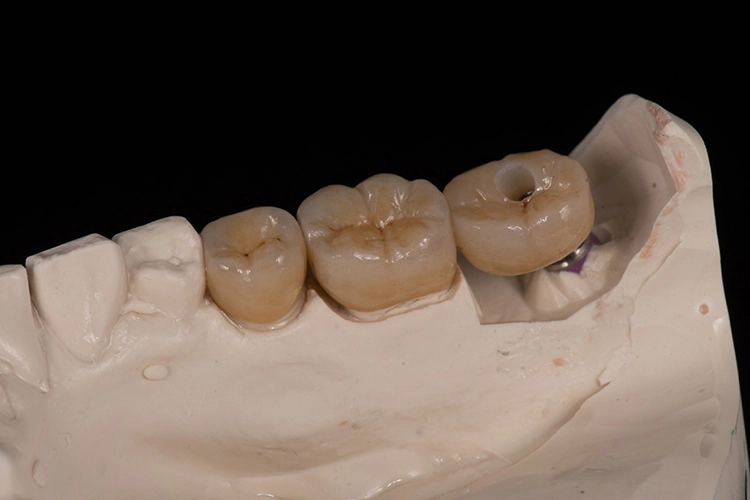

Bilder: Dr. Lampson / HannkerNach dem Ausgießen der Abformung sowie dem Scan des Gips- und Antagonistenmodells (Abb. 11a bis d) folgten das Kronendesign und die Fräsparametereinstellung per CAD/CAM-Programm (PowerMill Pro, Autodesk) (Abb. 12). Hergestellt wurden die Kronen aus Lithium-Disilikat-CAD/CAM-Blöcken (InitialTM LiSi Block, Farbe A2) (Abb. 13), die sich insbesondere durch eine hohe Opaleszenz bei hochtransluzenten (HT) Farbtönen auszeichnen und so auch ohne weitere Charakterisierung hochästhetische Ergebnisse erzielen.

Bilder: Dr. Lampson / HannkerNach 35-minütigem Schleifen (Exocad PowerMill CAM, DMG) wurde die Restauration aus dem Block entfernt und der Bereich der Anstiftung geglättet. Anschließend galt es, die Kronen auf den jeweiligen Formen und am Modell zu prüfen, wobei sich bereits eine perfekte Randpassung zeigte (Abb. 14 und 15). Danach erfolgte die Glaslötung der Implantatkrone auf das individuell angepasste Zirkonoxid-Abutment (Abb. 16).